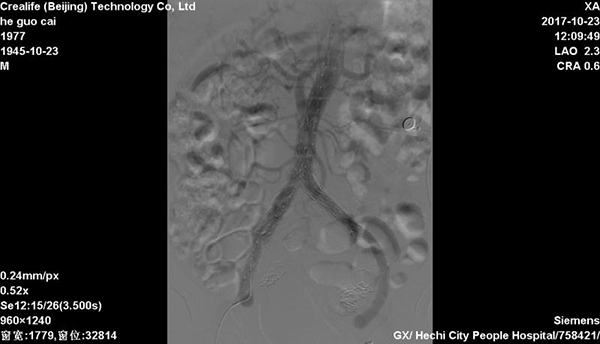

CT检查 10月23日,在华西医院黄斌副教授的现场指导下,胸心血管外科、放射科科、介入导管室等多科室医护人员的通力配合下,在局麻下完成经双侧股动脉腹主动脉瘤、双侧髂总动脉瘤、左侧髂内动脉瘤腔内覆膜支架修复术+左侧髂内动脉瘤、右侧髂内动脉弹簧圈栓塞术+球囊扩张术,手术过程顺利,患者获得成功救治。术后当日患者恢复饮食,第二天下床活动,1周后康复出院。

腹主动脉瘤腔内覆膜支架修复术后 腹主动脉瘤腔内覆膜支架修复术(EVAR)是目前治疗腹主动脉瘤的一种微创外科技术,其手术创伤较小,术后并发症少,使许多不能耐受手术的高危病人获得救治机会。但是EVAR治疗方案十分依赖腹主动脉的解剖学形态,血管腔内操作难度大,技术要求高。这次手术取得圆满成功,标志着我院胸心血管外科在腹主动脉瘤的诊治水平又上了新台阶。(文:韦连素)